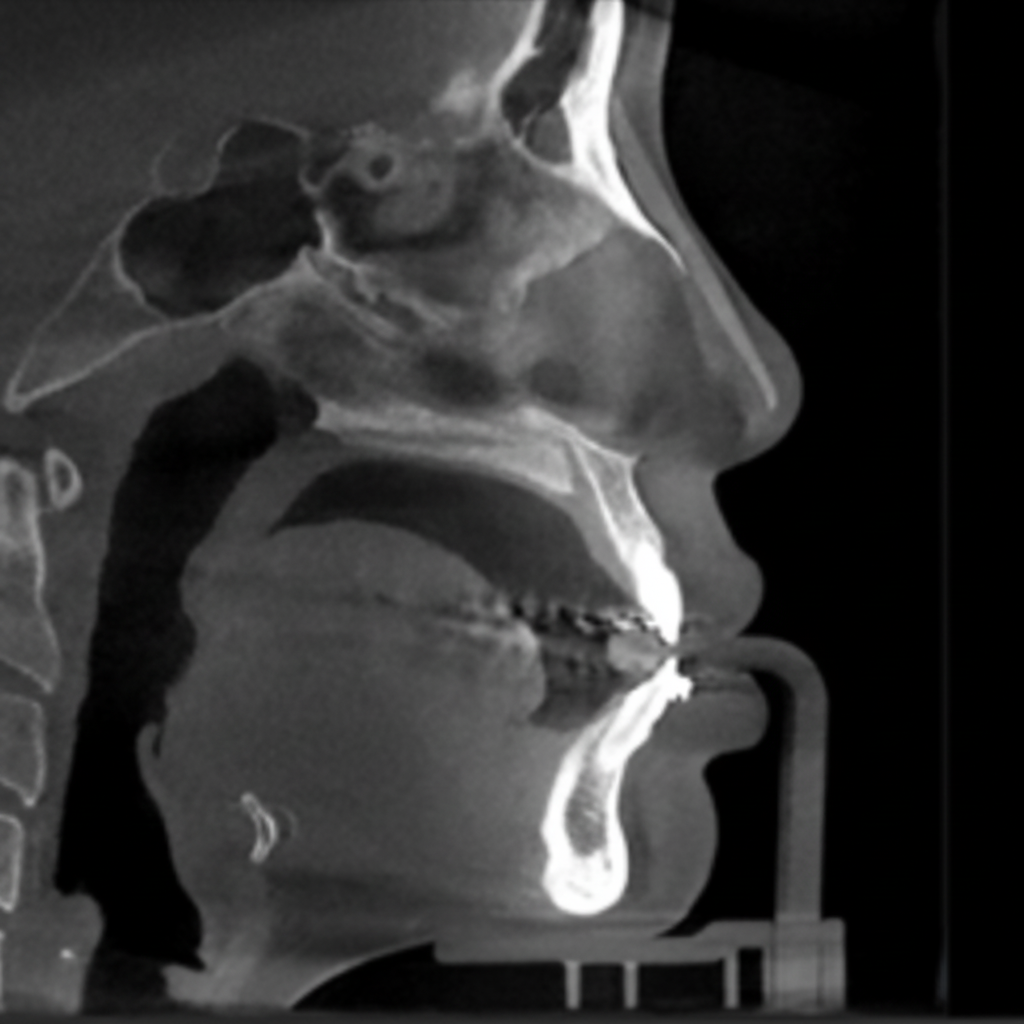

3D CT 분석에 의한 정밀진단

3D CT 분석을 통해 코뼈, 비중격, 연골길이, 내부변형 등 코 내부 상태에 대한 정확한 파악이 가능합니다.

코재수술의 경우 보형물의 위치, 고개기 대한 파악, 코골 연골과 변형 정도에 대한 예측을도 오차

다음 안정적인 결과를 도출합니다.

CT사진 2

3D-CT 정밀진단

3D-CT

정밀진단

겉으로 보이지 않는

코 뼈, 비중격 연골,

비대칭 유무 확인